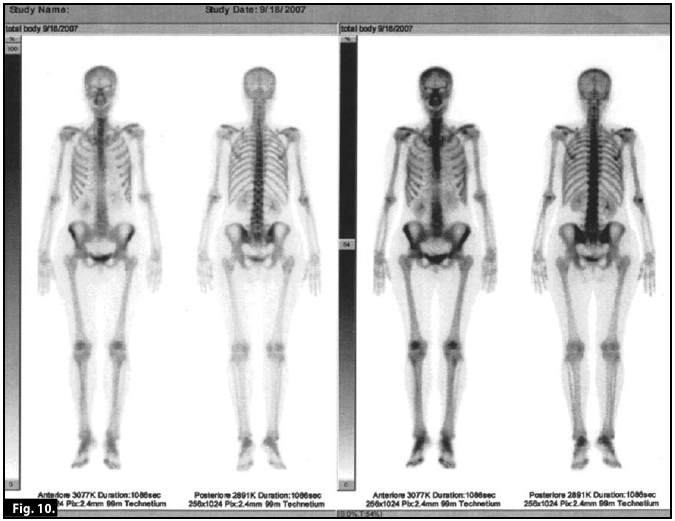

Scintigraphy